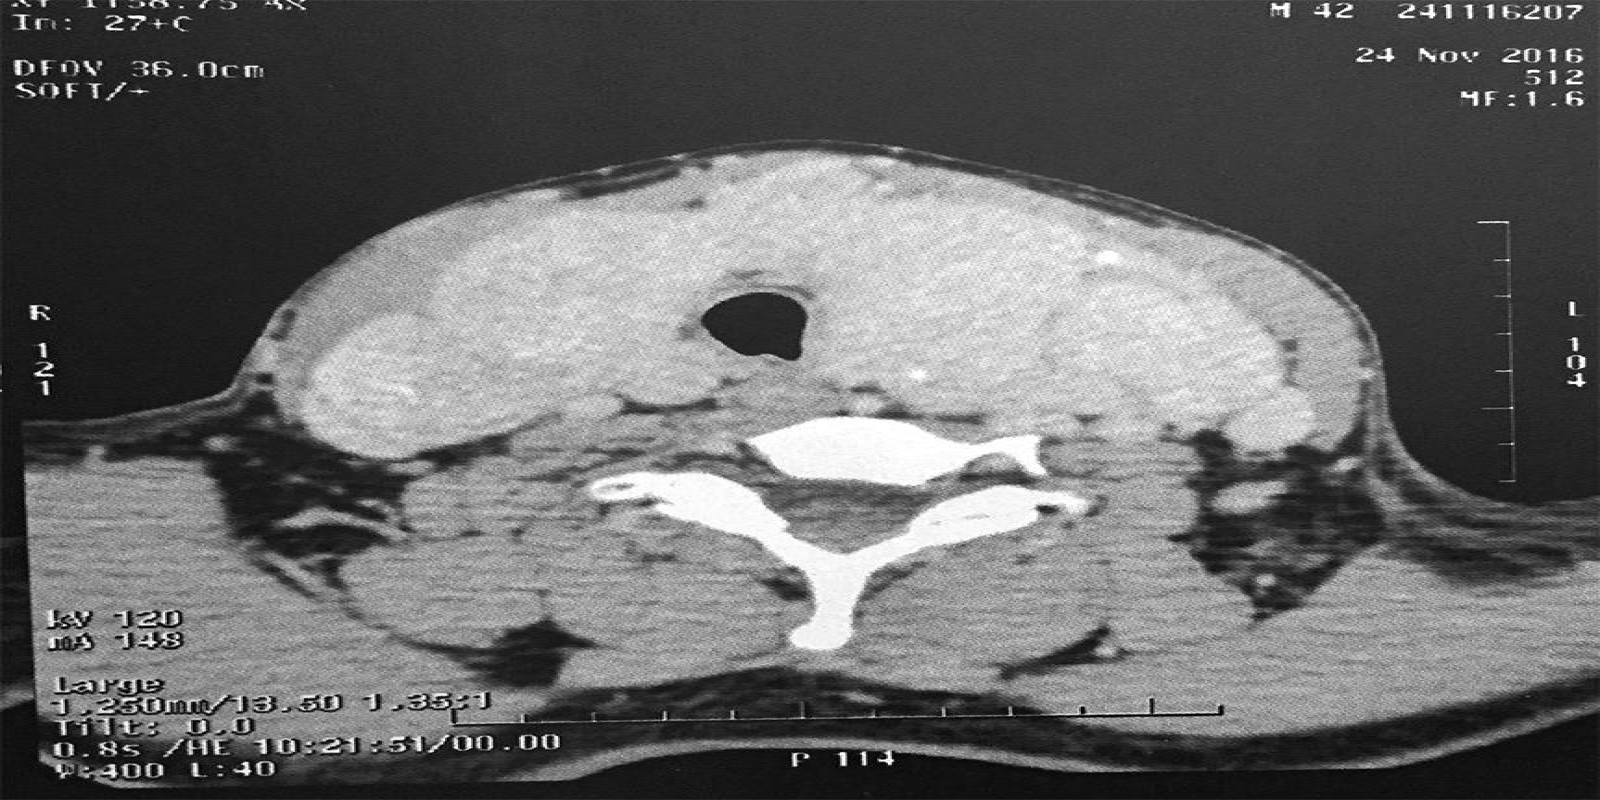

Caso Código 194A de Bócio Multinodular Atóxico

Cod.: 194A